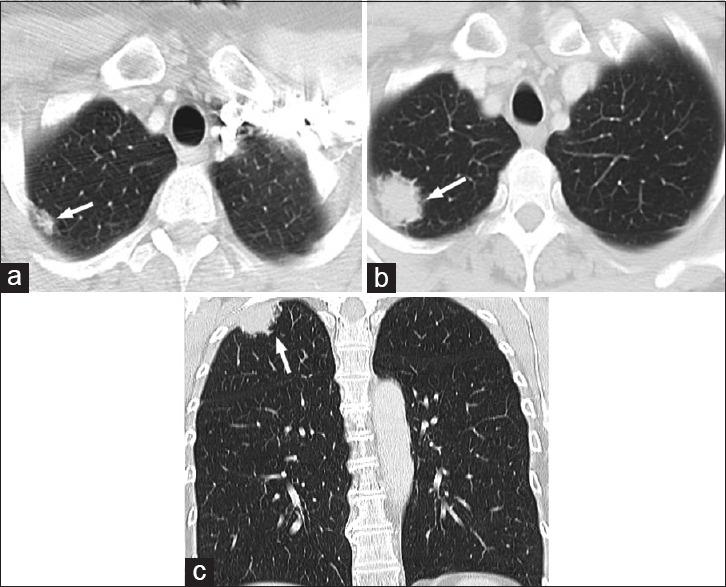

The term "small round blue cell" is frequently used as a cursory radiologic pathological correlation of aggressive tumors throughout the body. We present a pictorial essay of common and uncommon subtypes of small round blue cell tumors in the chest illustrating the characteristic radiologic findings of each lesion. In addition, we review the pathologic findings of each tumor subtype with characteristic hematoxylin- and eosin-stained photomicrographs and immunohistochemical and molecular studies. Represented tumors include small cell carcinoma, Ewing sarcoma, extranodal marginal zone B-cell lymphoma, embryonal rhabdomyosarcoma, desmoplastic small round cell tumor, and posttransplant lymphoproliferative disorder. Understanding and ability to recognize these lesions are essential to broaden the radiologist's differential diagnosis and help guide patient care.